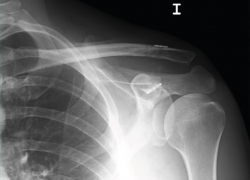

La exploración clínica se realizó mediante la valoración del denominado signo de la “tecla” (desplazamiento vertical) y del desplazamiento horizontal. Se completó el diagnóstico mediante radiografía simple anteroposterior (AP) comparativa de ambos hombros. En los casos de duda en relación con el grado de la lesión, esta proyección se realizó con la sujeción por parte del paciente de 2 kg de peso (Figura 1). No se creyó necesaria la realización sistemática de tomografía axial computarizada (TAC) ya que la exploración y la exploración bajo anestesia permiten establecer las direcciones y la importancia del desplazamiento. Tampoco se realizó resonancia, dado que la artroscopia permitiría, como así se demostró, diagnosticar posibles lesiones asociadas.